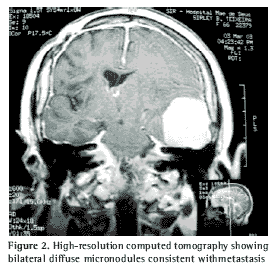

Simple radiogram of the thorax presented diffuse reticulonodular interstitial infiltrate. High-resolution computed tomography of the thorax (Figure 2) revealed micronodules disseminated through both lungs.